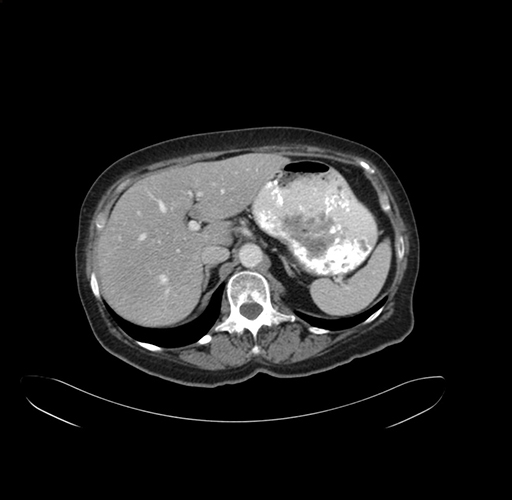

Pre-Chemo: Axial Venous

Axial Venous